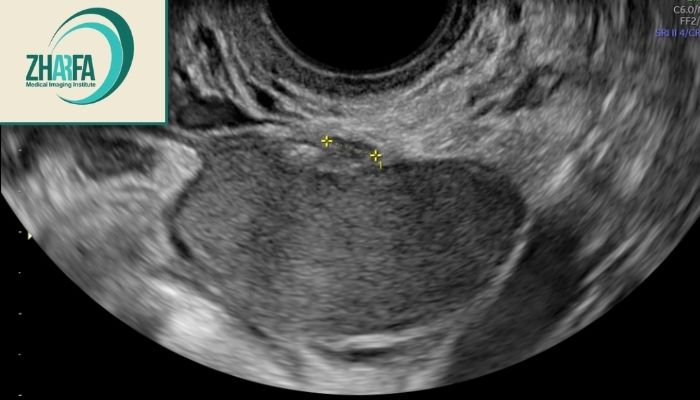

سونوگرافی ترانس‌واژینال (Transvaginal): دقیق‌ترین سونوگرافی برای یافتن کیست‌های آندومتریوما و ضایعات عمقی لگن است و نخستین انتخاب در بررسی بیماران محسوب می‌شود. مراکز مجهزی برای انجام سونوگرافی واژینال در شرق تهران وجود دارد که با دستگاه‌های پیشرفته و تفسیر تخصصی رادیولوژیست‌ها امکان تشخیص دقیق ضایعات آندومتریوزی را فراهم می‌کنند. این روش به‌ویژه برای بانوان دارای علائم درد لگن و ناباروری اهمیت فراوانی دارد.

نشانه‌های سونوگرافی این عارضه بسته به محل درگیری و شدت بیماری متفاوت‌اند اما چند الگوی مشخص وجود دارد که برای رادیولوژیست‌های باتجربه بسیار معنادار است. در ادامه مهم‌ترین علائم قابل مشاهده در سونوگرافی ترانس‌واژینال (TVS) و گاهی سونوگرافی شکمی آورده شده‌اند:

کیست آندومتریوما تخمدان: دیده‌شدن کیست با اکو داخلی یکنواخت و ظاهری شبیه «شیشه مات»؛ نشانه‌ بارز تجمع خون قدیمی در ضایعات آندومتر خارج رحم است.

چسبندگی و محدودیت حرکتی رحم و تخمدان‌ها: اندام‌های لگنی نسبت به هم حرکت ندارند و ممکن است تخمدان‌ها پشت رحم به‌هم نزدیک شوند (نشانه‌ی «تخمدان‌های بوسه‌زن»).

ضایعات عمقی (DIE): توده‌های هیپواکو، نامنظم و ثابت در دیواره رحم، واژن یا روده که نشان‌دهنده نفوذ آندومتر خارج رحم در بافت‌های عمیق است.

مایع آزاد در لگن: وجود مقدار کمی مایع در حفره داگلاس معمولاً ناشی از التهاب یا خونریزی ضایعات فعال آندومتر خارج رحم است.

تغییر شکل رحم یا تخمدان: چسبندگی‌ها باعث جابه‌جایی تخمدان یا خم‌شدگی رحم به سمت عقب می‌شوند؛ گاهی محور لگن نیز تغییر می‌کند.

درگیری مثانه یا روده: مشاهده ضخیم‌شدگی موضعی یا توده‌های هیپواکو در دیواره این اندام‌ها نشانه نفوذ ضایعات عمیق است.

Sliding sign منفی (کاهش تحرک اندام‌ها در سونو): هنگام فشار با پروب، رحم و تخمدان‌ها نسبت به هم حرکت نمی‌کنند؛ نشانگر چسبندگی شدید ناشی از آندومتر خارج رحم است.